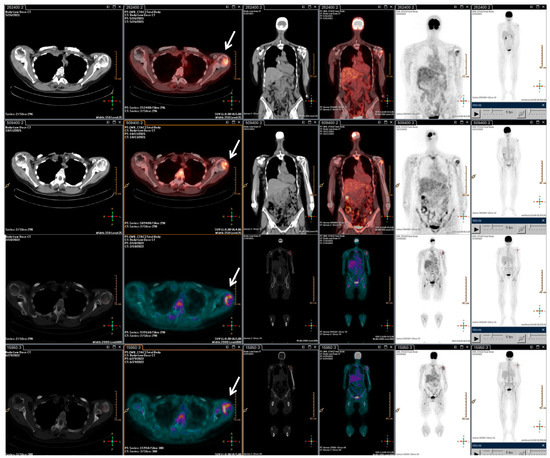

With the rising of the disease, trabectedin treatment was resumed and continued for an additional 21 cycles until January 2022, when a PET/CT scan revealed a slight metabolic progression in the left humeral head. Thus, in March 2022, radiotherapy treatment on the left humeral head was completed (20 Gy/5Fractions), and, considering the stable disease revealed in July 2022, the trabectedin administration was continued until February 2023 (Figure 3).

Figure 3.

F-18 FDG PET/CT performed after the radiotherapy retreatment. The main tumour lesions are indicated by white arrows.

Overall, the patient underwent a total of 73 cycles of trabectedin. Subsequently, due to disease progression in the left humerus, the patient underwent surgical treatment with prosthetic grafting. Despite the successful procedure, the patient experienced a rapid clinical decline characterized by a lung impressive progression disease, which led to her death shortly thereafter.